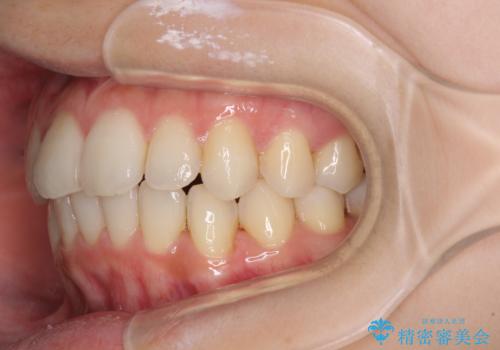

- 前歯のデコボコを気にして来院された患者様です。

叢生と捻転が随所に認められるものの、マウスピースで十分対応可能であったため、インビザラインにて矯正治療を行うこととしました。

マウスピース矯正は毎日しっかりと装着することがとても大切です。

こちらの方はしっかりと指示を守って装着してくださったため、予定通り治療を終えることができました。